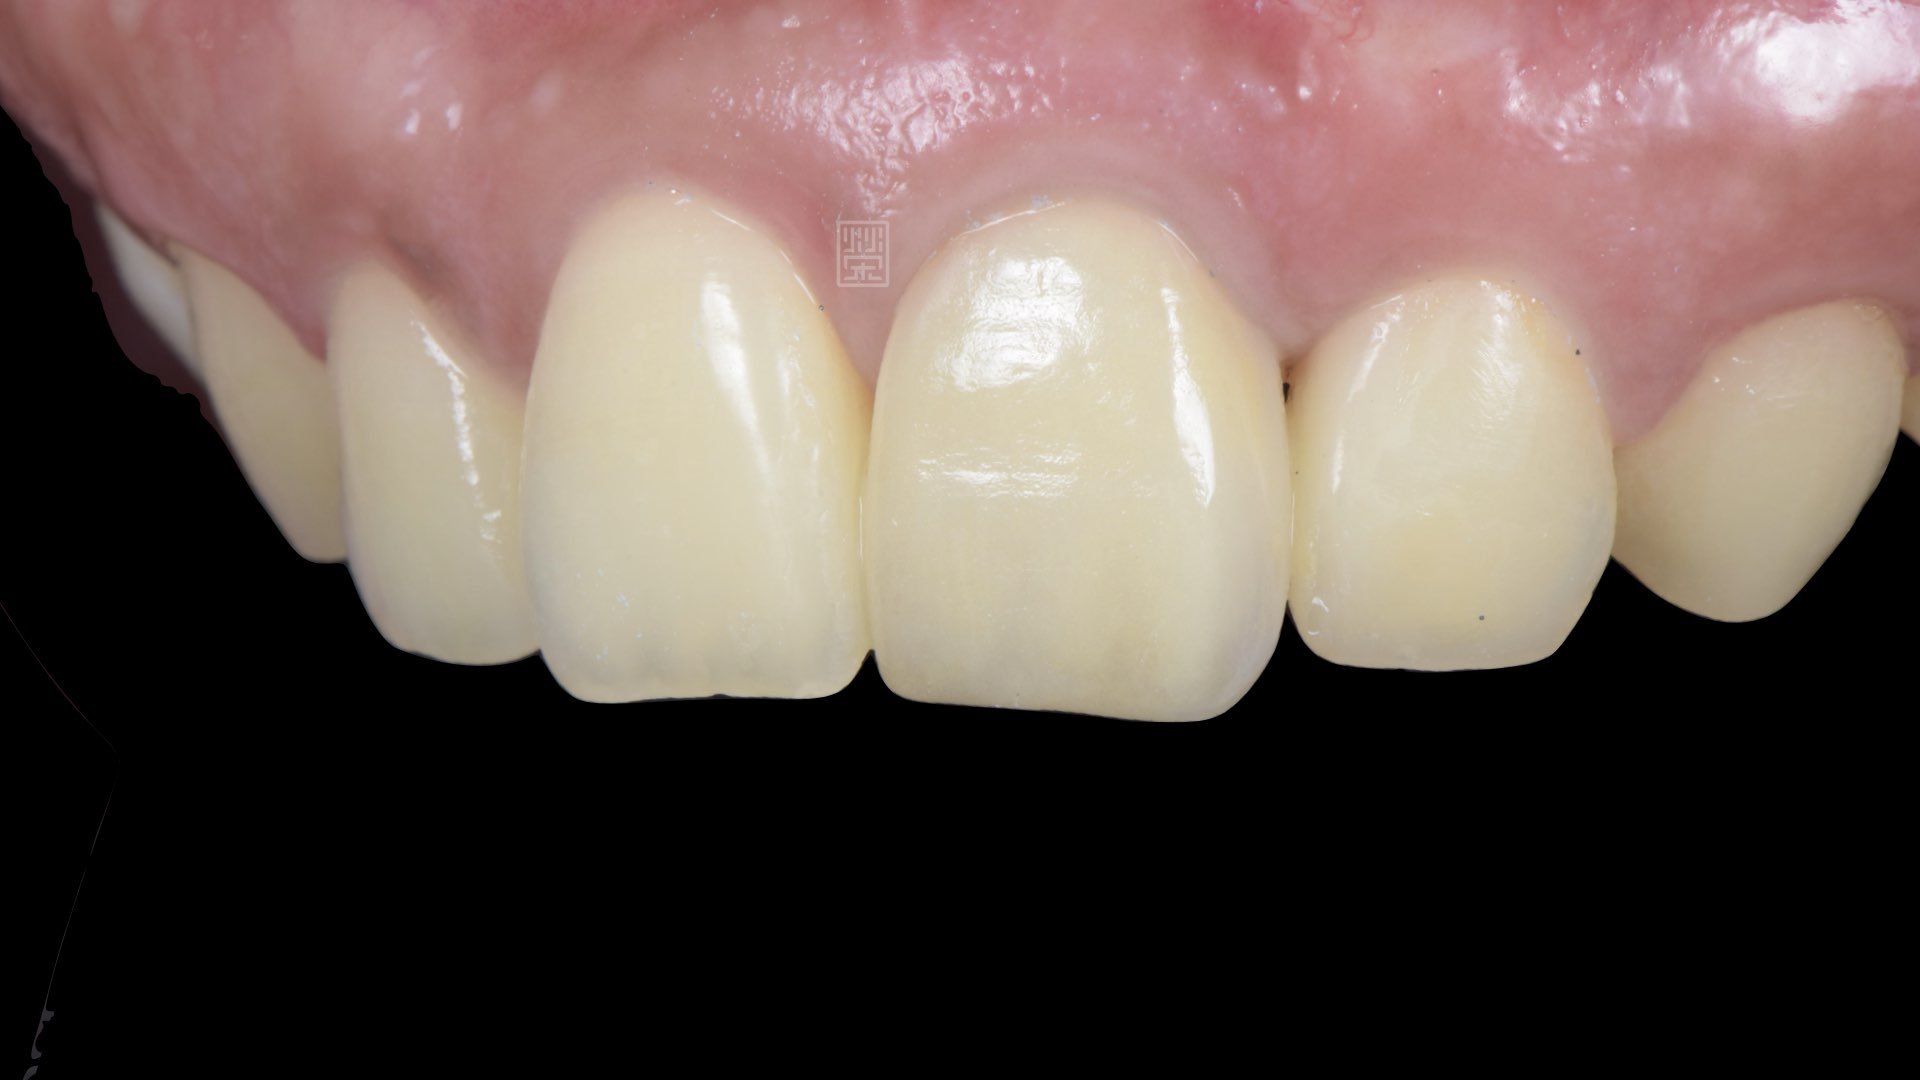

植牙全瓷冠

植牙完成